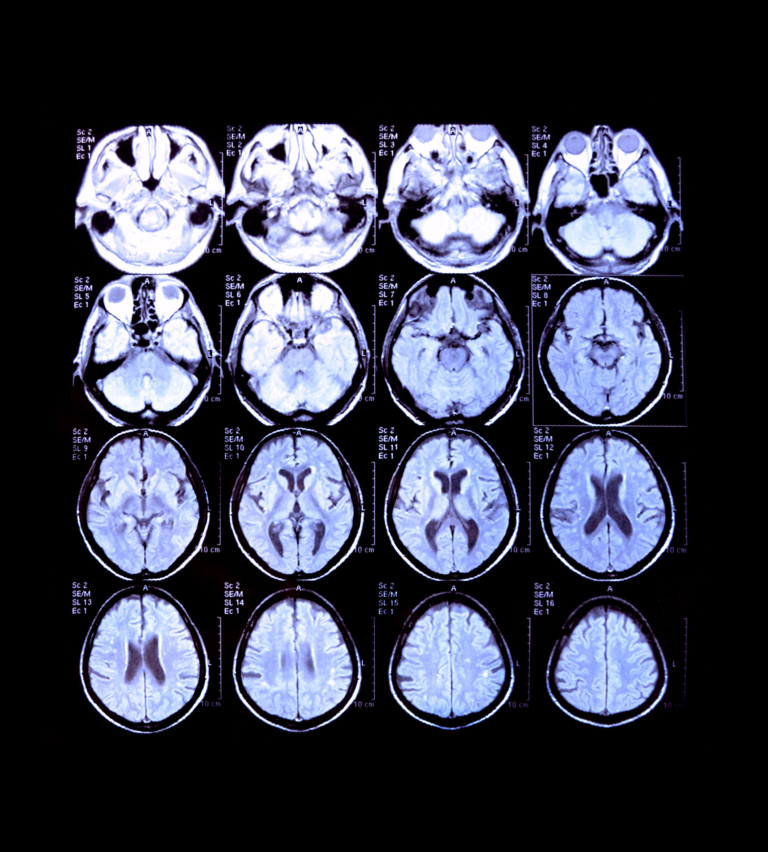

A grid of twenty medical images, likely MRI or CT scans of a brain, displayed against a black background. Each image shows an axial view of the brain, with varying shades of grey, white, and black representing different tissue densities. Some images show visible abnormalities or areas of interest, such as the white X-shaped area in one of the scans. Each image also has small white text labels in the upper left corner.

Automated brain atrophy mapping software using volumetric MRI imaging for definitive quantitative analysis for neurodegenerative cerebral diseases. Early intervention is known to significantly enhance recovery in neurodegeneration patients of all ages and especially in young-onset dementia cases (Rosser.N et al, 2010). But there is a severe lack of cost-effective and reliable prognostic tools, especially in the emerging economies.